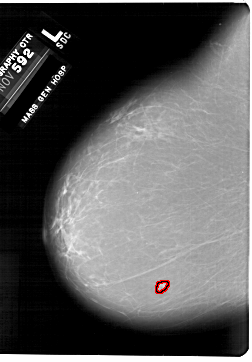

A_1876_1.LEFT_MLO

LEFT_MLO LINES 6871 PIXELS_PER_LINE 4291 BITS_PER_PIXEL 12 RESOLUTION 43.5 OVERLAY

FILE: A_1876_1.LEFT_MLO.OVERLAY

TOTAL_ABNORMALITIES 1

ABNORMALITY 1

LESION_TYPE MASS SHAPE LOBULATED MARGINS MICROLOBULATED

ASSESSMENT 4

SUBTLETY 3

PATHOLOGY BENIGN

TOTAL_OUTLINES 1

BOUNDARY